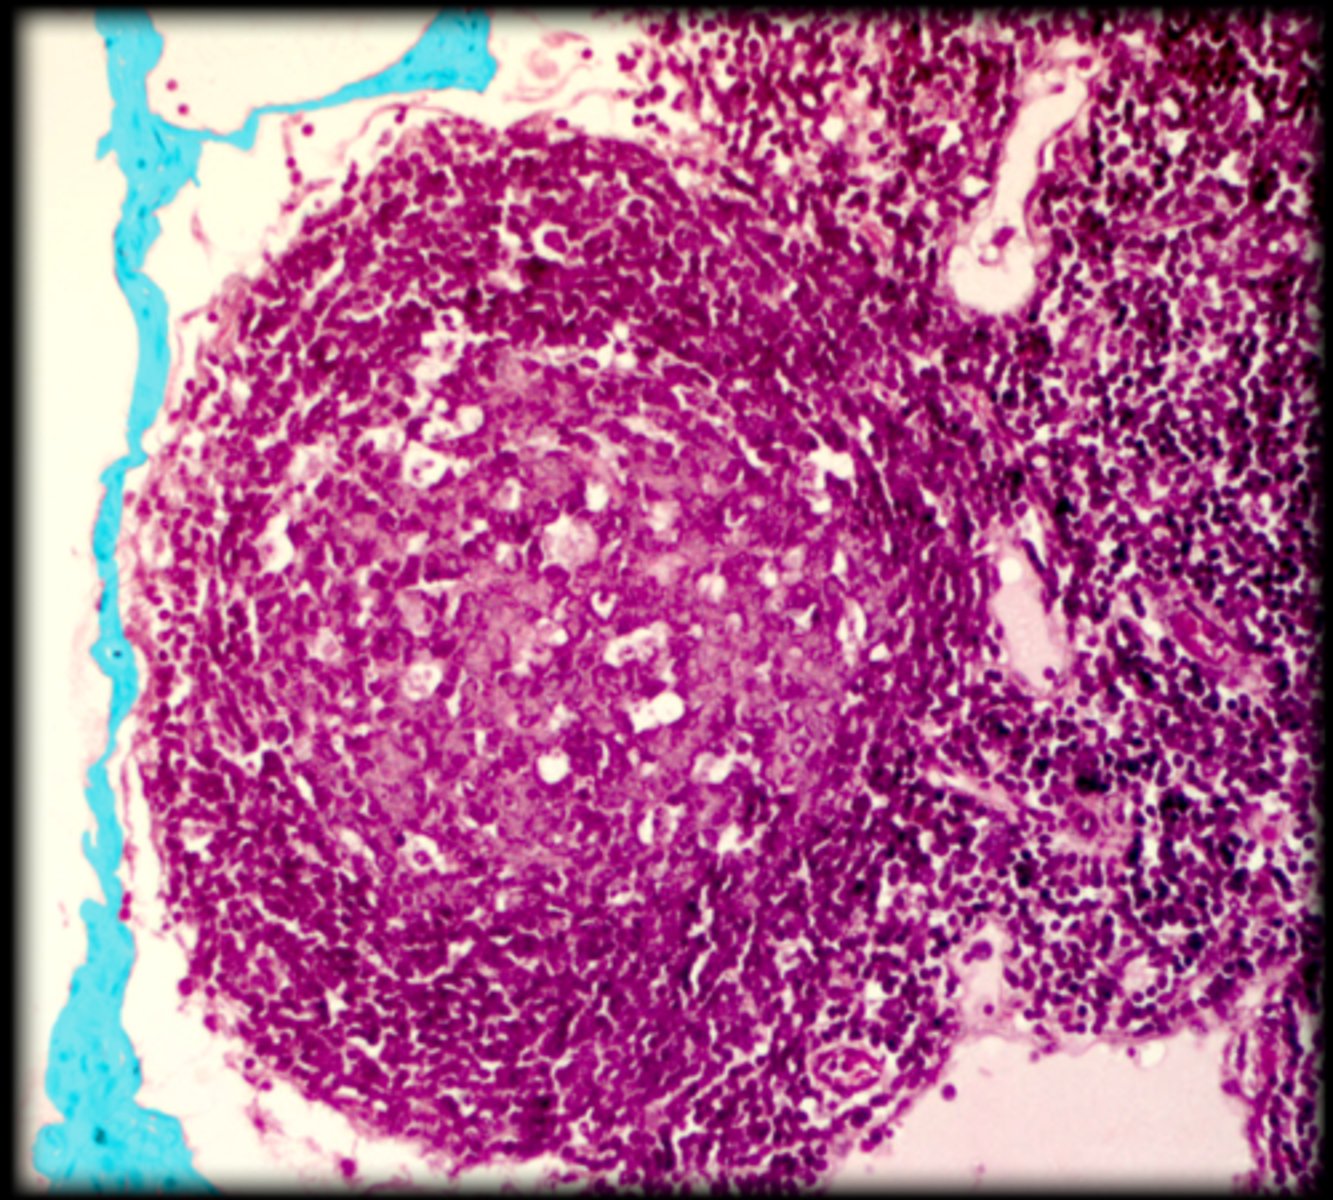

central white pulp

Spleen

red pulp

white pulp